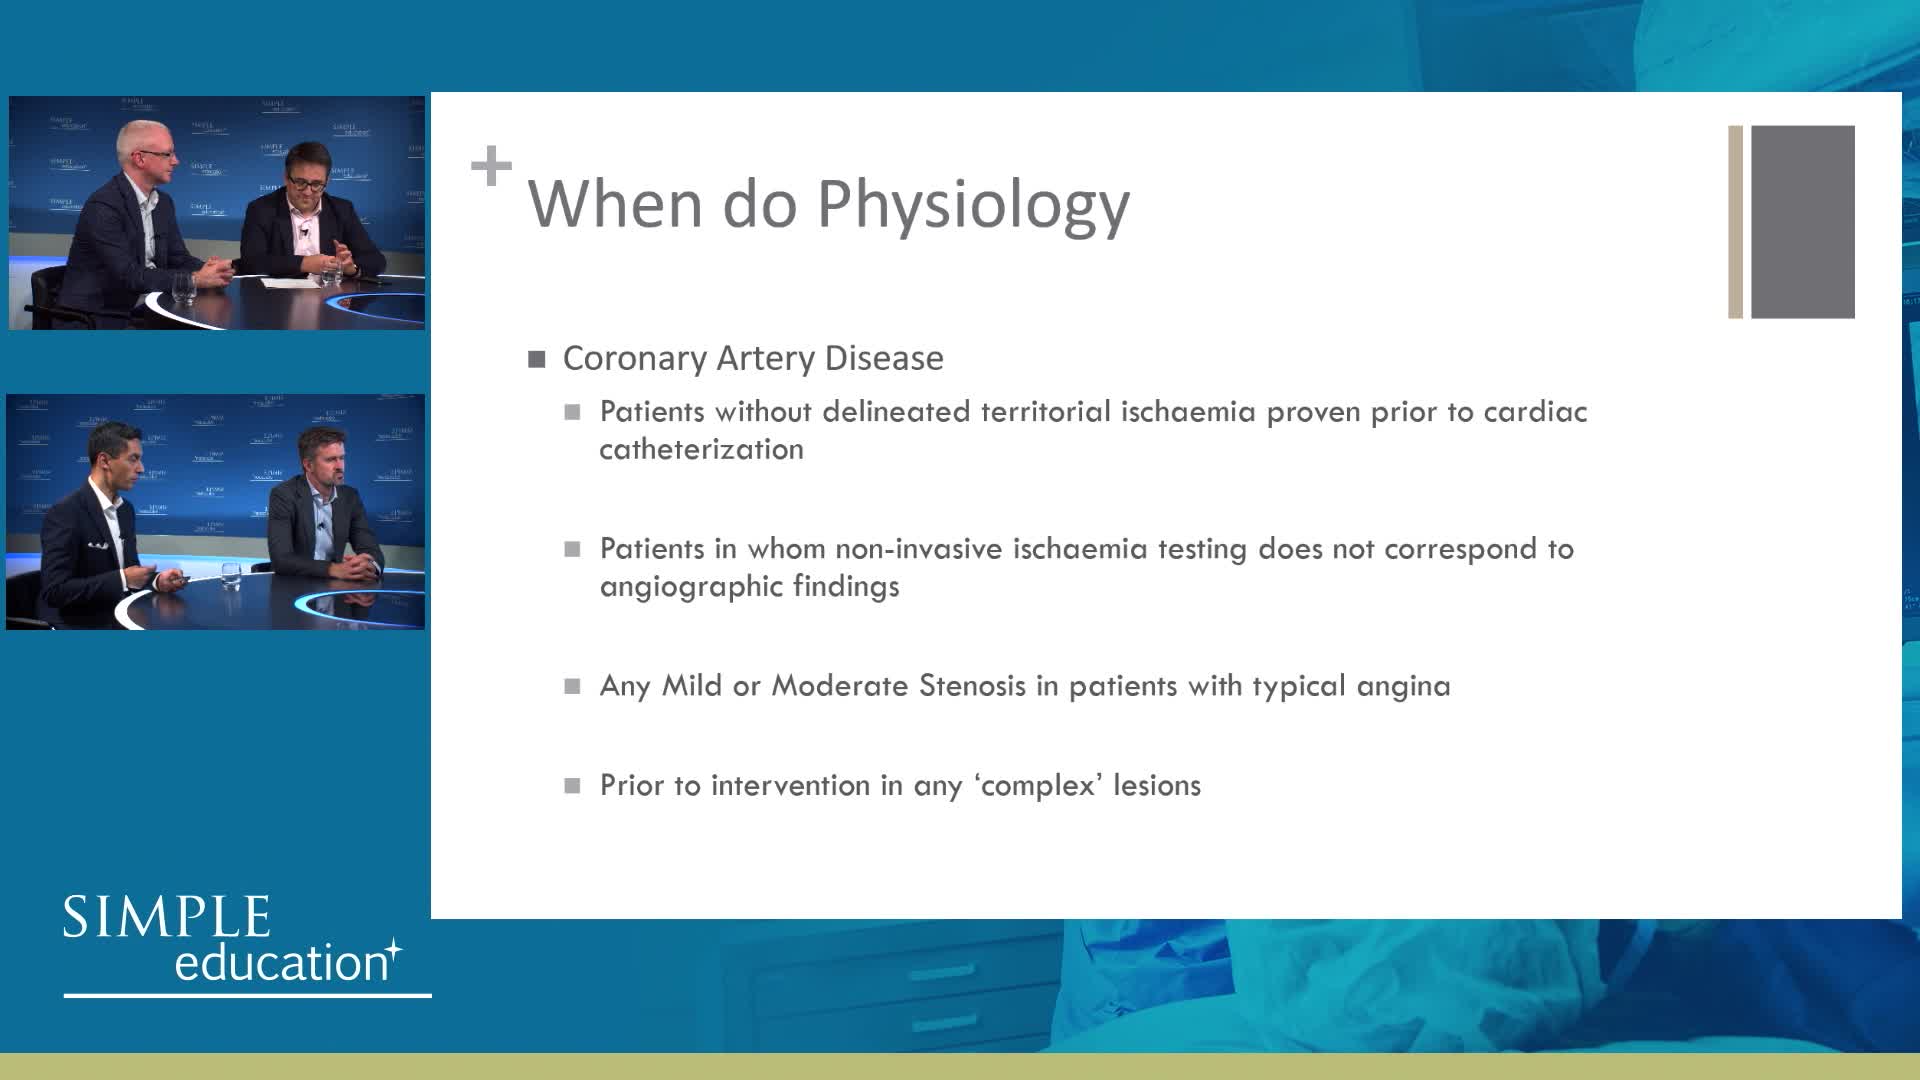

Essential steps for physiology-based PCI planning and guidance - Dr Allen Jeremias

Best practices and personalised medicine in complex PCI - Prof Javier Escaned